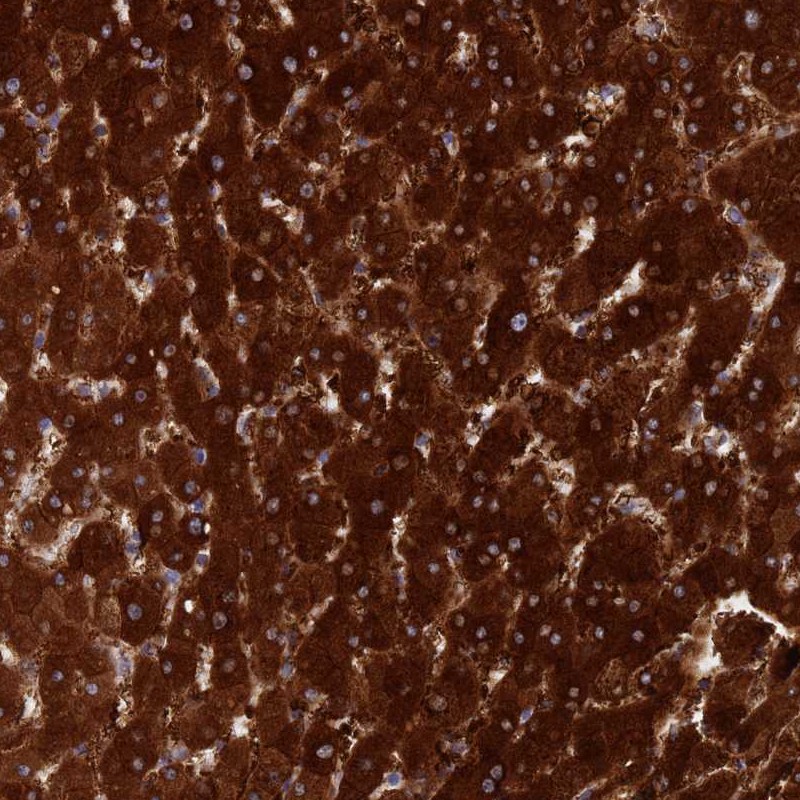

Immunohistochemical staining of human liver shows strong cytoplasmic positivity in hepatocytes.